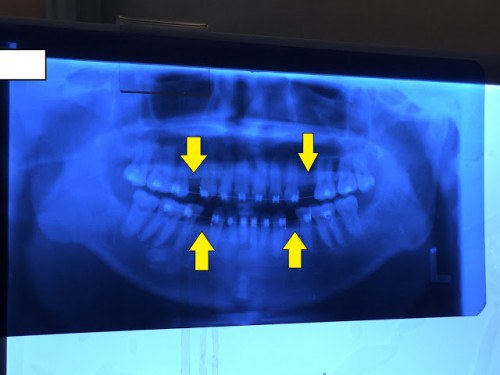

ตำแหน่งฟันกลามน้อยด้านล่าง ที่ต้องถูกถอนออกไป

ตำแหน่งฟันกลามน้อยด้านบน ที่ต้องถูกถอนออกไป

2. ปักเจ้า Orthodontics Mini-screws ลงไปในเหงือกทั้งด้านบนและด้านล่าง (ของผมปัก 4 ตัว บน 2 ตัว ล่าง 2 ตัว)